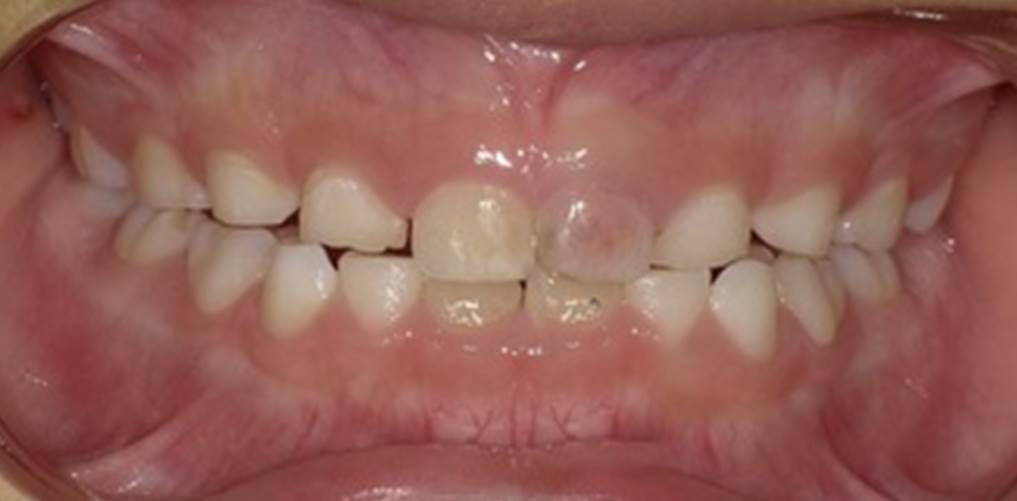

地域柄でしょうか、当院にはご高齢の方が多く来院されますが、近隣に幼稚園がある関係もあり、小さなお子様の歯科治療の相談が、最近では増えてきています。本日来院されたお子様は、数週間前に自宅で受傷し、ここ数日間で歯の色の変色に気が付いた、という患者様でした。

写真の例のように、歯の内部の血管や神経が透けるような様相を呈する歯の変色であることから「ピンクスポット」と呼ばれます。歯の「内部吸収」という状況になると、このピンクスポットが出現することがあります。

歯の「内部吸収」とは、歯の内部にある神経の側から、象牙質が破壊されて歯質が薄くなってしまうことを指します。打撲などの外傷が引き金となり、内部吸収を起こして歯が薄皮一枚になってしまい、内側の組織が透けて見えるため、ピンク色に変わってしまうのです。症状は無く経過することがほとんどで、歯の色が変ってきたり、たまたま撮影したエックス線写真で気づくことが多いのです。早い段階で吸収の程度が少なければ、ダメージを受けてしまった神経の処置をして内部吸収の進行を抑制し、歯を残すことができますが、吸収してしまった歯質は元に戻すことができません内部吸収が進行すると稀ですが抜歯となる場合があります